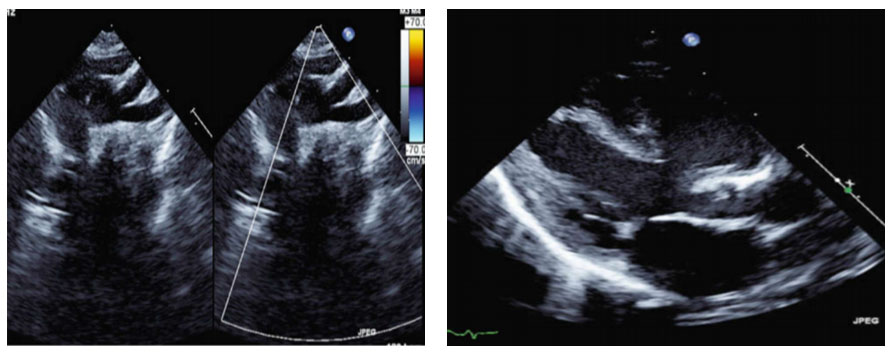

Détresse cardiorespiratoire néonatale

Vignette Clinique : Nouveau né de sexe masculin,  admis en  néonatologie   à   J2  de vie  pour défaillance cardio-circulatoire et respiratoire aigue nécessitant l’intubation naso-trachéale.

Auscultation cardiaque : souffle  systolo-diastolique sous claviculaire   Gauche

Pouls fémoraux abolis.

La saturation mesurée au membre supérieur droit est à 99%  et  celle  du  membre  inférieure droit est de  55  %  sous 100% d'oxygène

La radiographie de thorax :   une cardiomégalie, une surcharge pulmonaire et absence d’empreinte thymique.